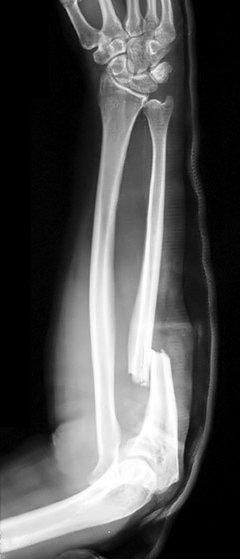

Monteggia's fractures

Definition: these are fractures of the proximal third (usually) of the ulna with associated dislocation of the radial head. Classified as:

Type I - fracture with anterior radial head dislocation. This is the most common (60%).12

Type II - fracture of the proximal ulna with posterior or posterolateral dislocation of the radial head (15%).12

Type III - fracture of the ulnar metaphysis with lateral or anterolateral dislocation of the radial head (20%).12

Type IV - fracture of both the radius and ulna at their proximal third with anterior dislocation of the radial head (5%).12

Mechanism of injury: usually caused by a fall on to an outstretched, extended and pronated elbow, or by a direct blow.

Presentation: acute, severe pain and swelling in the forearm and elbow. Damage may occur to the posterior interosseous nerve.

Monteggia fracture

By Jane Agnes (own work), via Wikimedia CommonsInvestigation: X-ray the entire length of the radius and ulna, including the wrist and elbow - AP and lateral views are usually sufficient but there may be a need for radiocapitellar views.

Management: in adults, immobilise the joint in a splint and refer for open reduction and internal fixation. Most paediatric Monteggia's fractures are treated closed.13

Isolated proximal ulnar fractures are rare. Always examine for a Monteggia's fracture/dislocation.